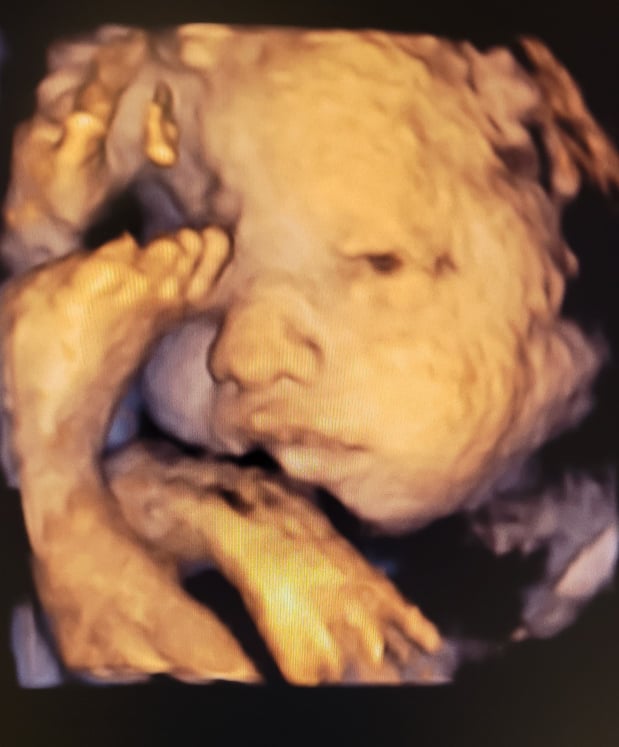

Tasha Crump, is registered by the American Registry of Diagnostic Medical Sonographers (ARDMS) and have over 18 years experience in medical diagnostic sonography specializing in Maternal Fetal Medicine. She is a highly proficient in the art of 3D 4D ultrasound. Tasha has practiced and trained in NYC's top ranked hospitals including Columbia Presbyterian. At Love at First Sight Imaging Studio you'll be in a very comfortable and calming atmosphere for you and your family to bond with your baby. We have state of the art equipment with HD Live to image unbelievably realistic views of your baby. You will fall in Love at First Sight.